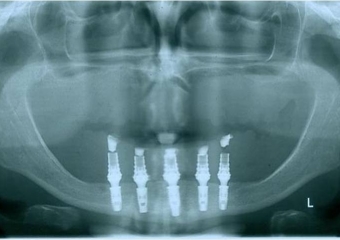

Raio x após prótese imediata fixa inferior e nova prótese superior, provisórias instaladas - Clínica Cliniface

Raio x após prótese imediata fixa inferior e nova prótese superior, provisórias instaladas